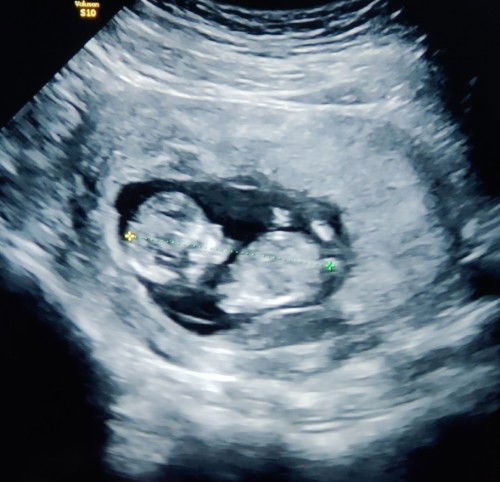

ผมในฐานะคุณพ่อป้ายแดง และคุณแม่ป้ายแดง ที่กำลังจะมีลูกน้อย เจ้าตัวเล็กกำลังโตวันโตคืนอยู่ในท้องของคุณแม่ คุณพ่อ-แม่ ก็คอยดูแล บำรุง รักษา เป็นอย่างดีที่สุด ทางผมและภรรยา ขอเป็นกำลังใจให้กับ คุณแม่ ทุกๆคน รวมไปถึงคุณพ่อทุกๆคนด้วยครับ ขอให้ทุกๆคนจงมีแต่ความสุขความเจริญ สุขภาพแข็งแรงตลอดไปครับ❤ #วันแม่2565